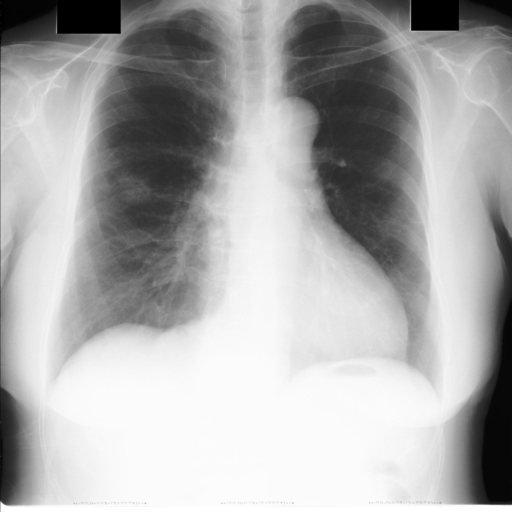

Chest X-ray, or CXR, is widely used in diagnosing abnormal conditions in the chest and nearby structure. Radiologists routinely perform cardiothoracic ratio (CTR) measurement on antero-posterior chest radiographs to diagnose Cardiomegaly, a condition that is strongly correlated with both congenital and congestive heart diseases. Although most Picture Archiving and Communication Systems (PACS) include drawing tools to aid the assessment of CTR, the process is still often labor intensive and time consuming. Manual labeling of organ boundaries and calculation of CTR is prone to error and can lead to faulty interpretations.

In this work, we explore an automatic approach to calculate CTR from chest X-ray film utilizing deep learning models. Using an image segmentation network based on U-Net with VGG16 encoder [1], we extract lung and heart regions from the CXR film. The heart and lung diameters are then calculated from the segmented regions.

Chest radiography is the most common tool for detecting cardiomegaly due to the low cost and high availability of devices to obtain chest X-ray images. From chest X-ray images, radiologists employ CTR as one of the most important indicators of cardiomegaly due to the simplicity of the calculation. CTR of a chest X-ray image is calculated as cardiac diameter (the diameter of the heart) divided by the thoracic diameter (the diameter of the chest). Specifically, CTR can be calculated from three measurements, , the midline-to-right heart diameter, , the midline-to-left heart diameter, and , the internal diameter of chest [2, 3], as

where and is measured from the greatest perpendicular diameter from midline to right and left heart border, respectively. Figure 1 visualizes the details of CTR calculation. A CTR value of is generally considered to indicate the upper limit of normal.

3.5 Cardiothoracic Ratio Calculation

After obtaining the masks, we calculate CTR with equation 1. We calculate cardiac diameter, , by finding the extreme points on the x-axis of the heart mask and calculate their x-axis distance. Thoracic diameter, , is calculated from extreme points from the lung mask. Figure 4 demonstrates the calculation of each component.

Figure 6 shows examples of our CTR calculation, where CTR values along with their , and measurement points are correctly identified. In this image, cardiomegaly is correctly detected by CTR value of .

Figure 7 shows cases where our CTR calculation algorithm is incorrect due to failure to obtain accurate heart mask.

However, upon manual inspection of the images, we found a relatively high number of mild cardiomegaly cases that are not included in the dataset labels. Figure 8 shows sample chest X-ray images containing no-cardiomegaly labels with detected CTR values on range. This reflects the general sentiment that dataset labels are noisy and may contain errors, making it harder to analyze our algorithm. It also illustrates the value of an algorithmic "second opinion" to catch potential errors from both human and NLP algorithms used to generate the labels.